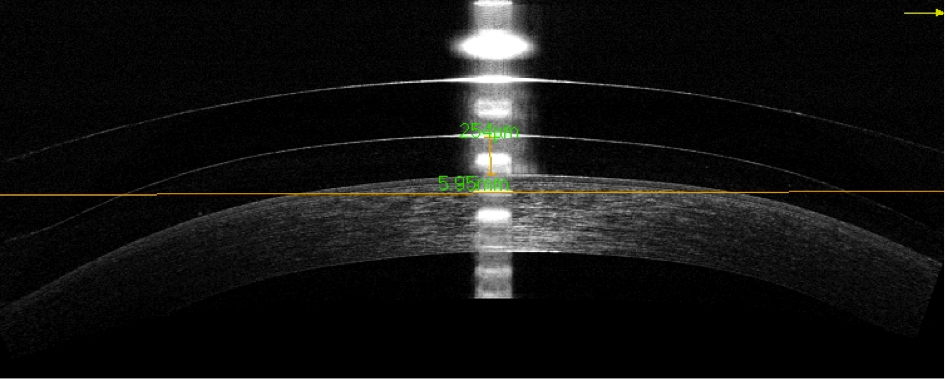

Abbildung 13: Änderung der zentralen Überbrückung durch Erhöhung der Scheiteltiefe der x1

Der obere Teil der Abbildung zeigt eine i-MATRIX mit einer BC 7,6 mm im Durchmesser 17,5 mm und einer Standard Scheiteltiefe der Limbalzone (x1 = STD). Die gemessene zentrale Überbrückung mit dem Optovue OCT beträgt ca. 250 μm. Der untere Teil der Abbildung zeigt hingegen eine i-MATRIX mit einer BC 7,6 mm im Durchmesser 17,5 mm bei der die Scheiteltiefe x1 um 200 μm erhöht wurde. Die zentrale Überbrückung erhöht sich dadurch, um den Betrag der Änderung der Scheiteltiefe x1, auf ca. 450 μm.

Der obere Teil der Abbildung 13 zeigt eine i-MATRIX mit der BC 7,6 mm im Durchmesser 17,5 mm und x1 = STD. Die Überbrückung im Zentrum beträgt mit dieser Sklerallinse ca. 250 μm.

Anschliessend wurde dem Patienten eine Sklerallinse aufgesetzt, bei welcher die Scheiteltiefe x1 um 200 μm erhöht wurde (Abb. 13 unten). Alle anderen Parameter wurden beibehalten. Durch die Erhöhung der Scheiteltiefe x1 um 200 μm, erhöht sich ebenfalls die Überbrückung im Zentrum von ca. 250 μm auf ca. 450 μm.